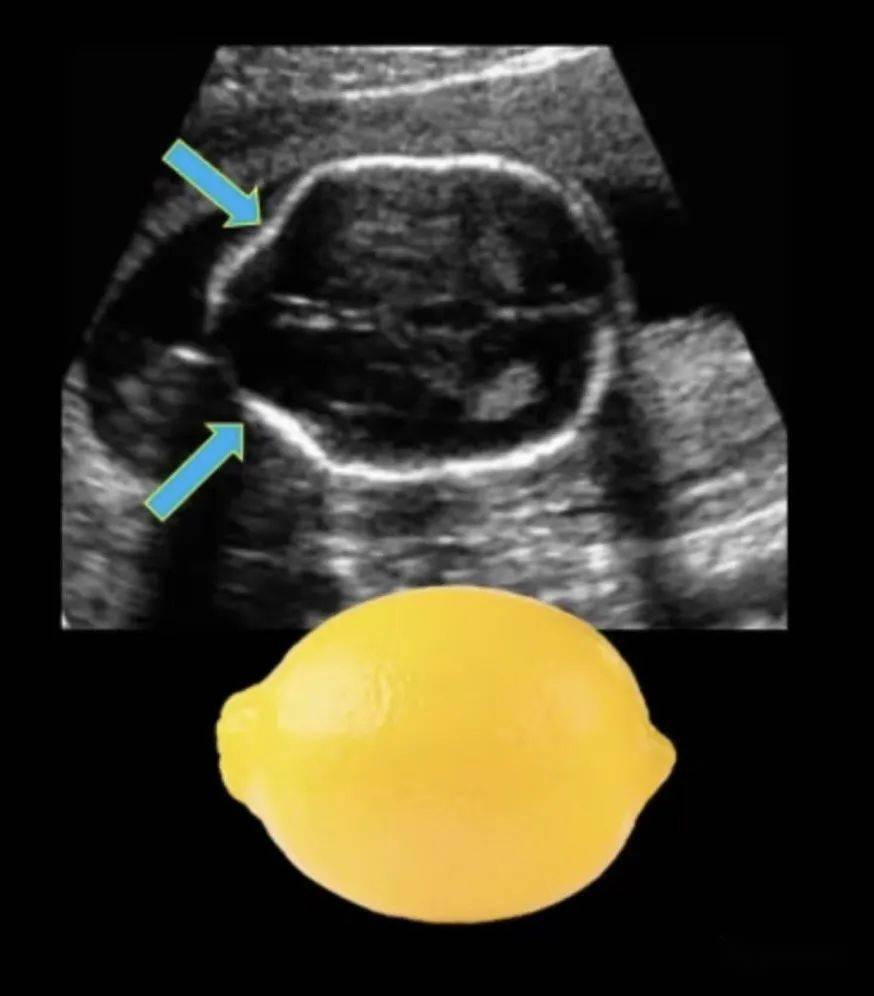

胎儿柠檬头

这是柠檬形胎头吗?附三维彩超报告

胎儿颅骨形状异常之柠檬头和草莓头

"柠檬头"

胎头柠檬征转载

78柠檬征开放性脊柱裂中,97%胎儿在24周前有香蕉小脑征.

胎儿柠檬头是什么意思3

柠檬头和草莓头_胎儿_小脑_形状

柠檬头,脑积水,脊柱裂所以四维彩超现在已经成为检测胎儿健康的一大

柠檬头合并脊柱裂一例